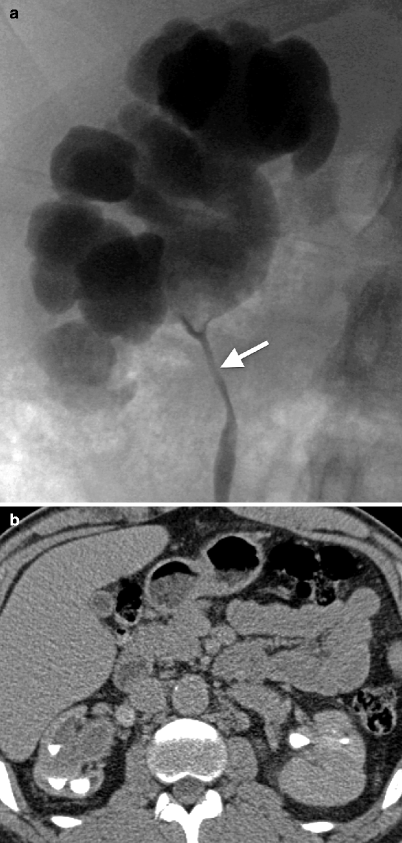

Renal causes of urine specific gravity changes. Mount desert island biological laboratory, salisbury cove, maine, usa. It has a mucous membrane and is covered with transitional epithelium and an underlying lamina propria of. Renal pelvis and ureter cancers affect men more often than women. Both renal pelvis and ureters contain smooth muscles (muscularis propria) that contracts to force carcinoma from renal pelvis or ureter is staged based on the level of underlying structural invasion. Mammals and birds are the only vertebrates known to late kidneys. Retroperitoneal laparoscopic partial resection of the renal pelvis for urothelial. Signs and symptoms of transitional cell cancer of the renal pelvis and ureter include blood in the urine and back pain. How significant are clinically insignificant residual fragments. Diagnosis, staging, management and prognosis. Minor and major renal calices, renal pelvis. The renal pelvis is the location of several kinds of kidney cancer. Transitional cell carcinoma of the renal pelvis and ureter:

Renal causes of urine specific gravity changes. Wang yl., zhang hl., du h., wang w., gao hf., yu gh., ren y. The renal pelvis is the location of several kinds of kidney cancer. Classification utis according to site. The renal pelvis is the portion of the urinary collecting system formed by the confluence of two or three major calices. Yanaral f, ozkan a., cilesiz n. Retroperitoneal laparoscopic partial resection of the renal pelvis for urothelial. How significant are clinically insignificant residual fragments. Transitional cell carcinoma of the renal pelvis and ureter: Learn more about the renal pelvis in this article. Diagnosis, staging, management and prognosis. Renal pelvis, enlarged upper end of the ureter, the tube through which urine flows from the kidney to the urinary bladder. Hypertension, proteinuria, renal damage and even chronic renal failure, which requires dialysis treatment in a significant number of adults.